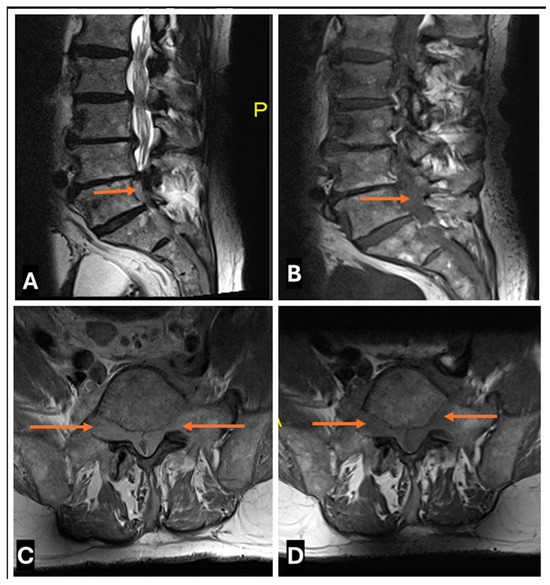

- Neurolymphomatosis describes intraneural spread of lymphoma and appears as diffuse enlargement of nerves, plexuses, spinal cord, and cauda equina. It shows more homogeneous enhancement than PNSTs and may be associated with lymphadenopathy or a known history of lymphoma [63] (Figure 20 and Figure 21).